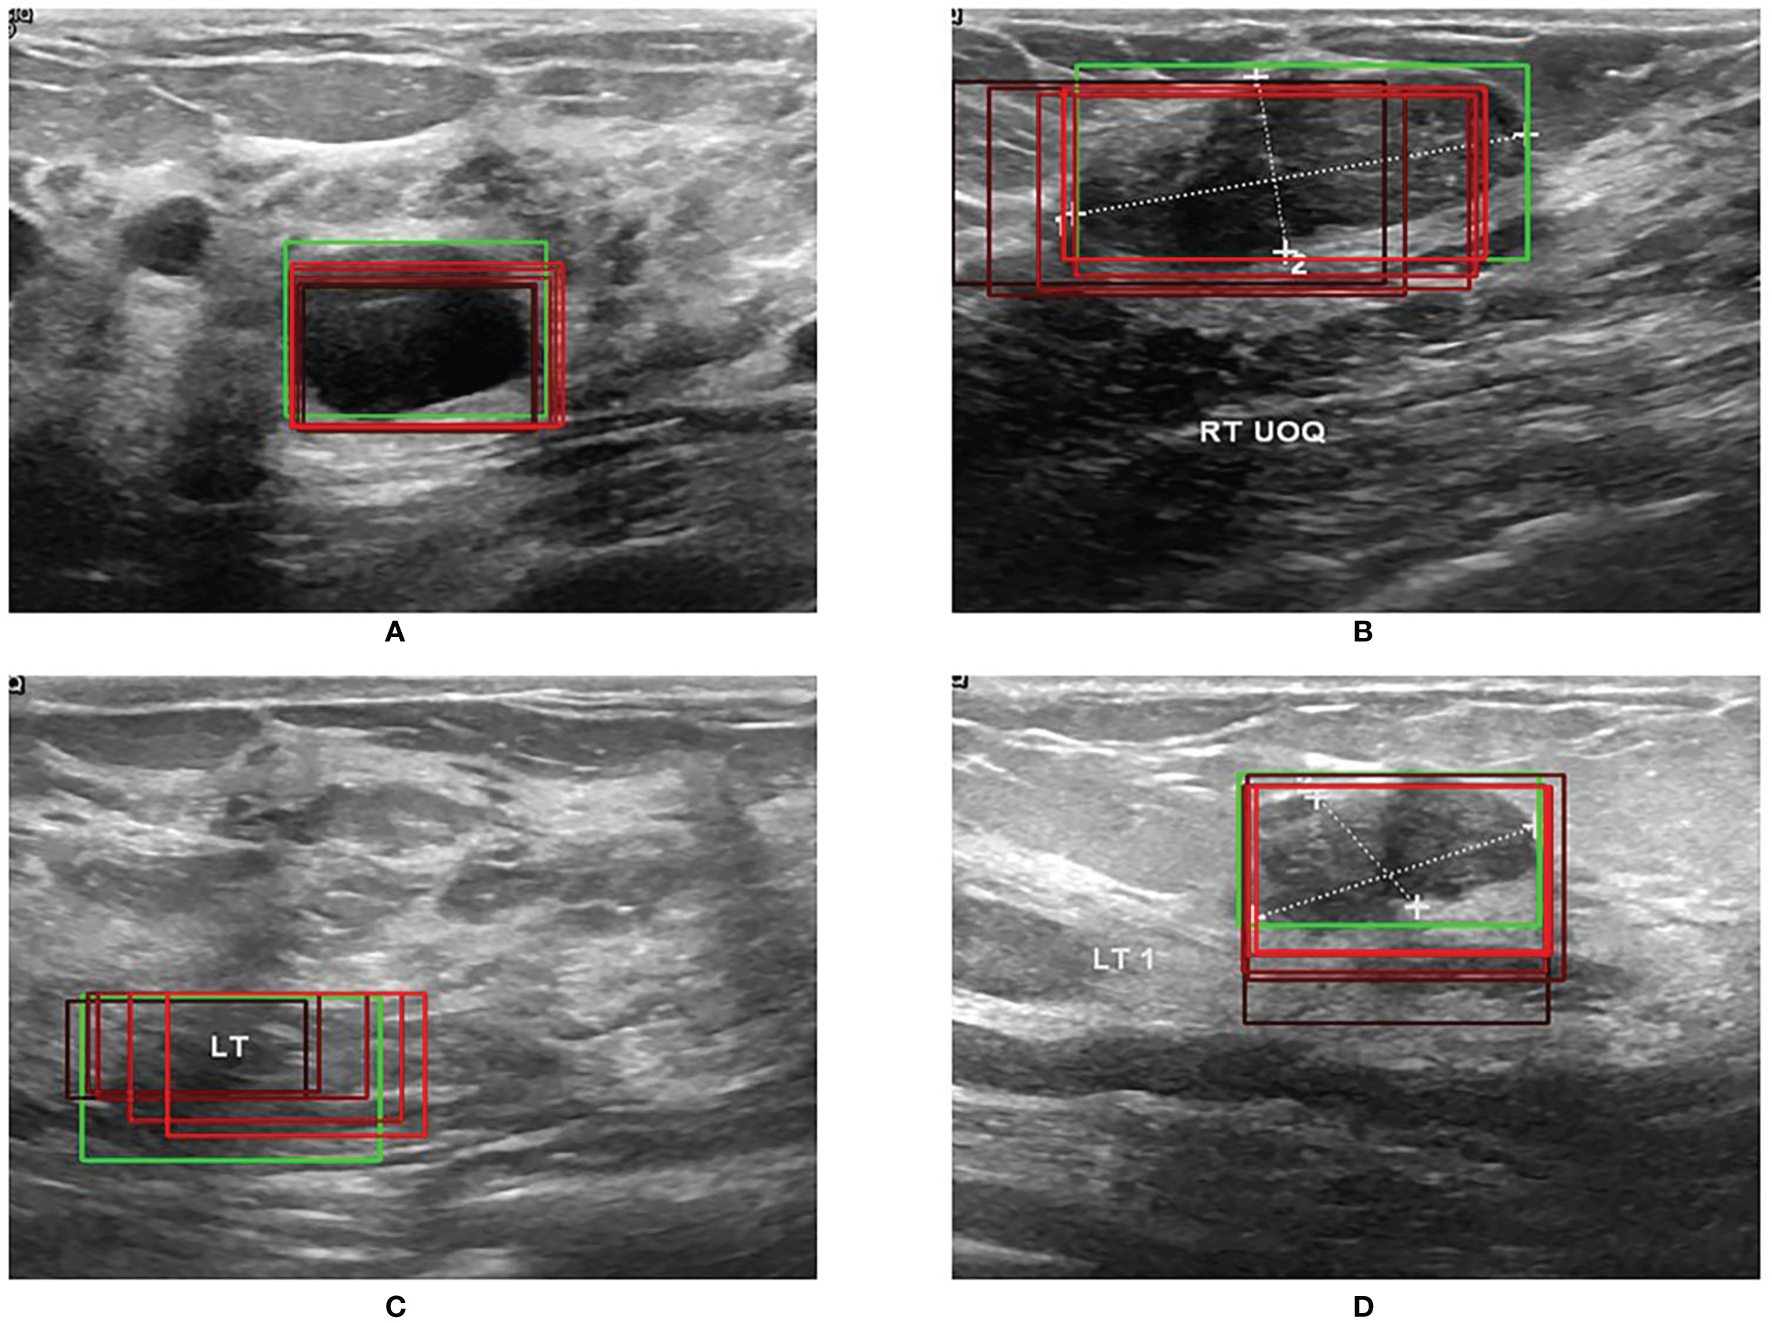

Figure 5 shows the results of RoI extraction, in which (A) is the original image, (B) is the edges obtained by the Canny edge detector, (C) is the RoIs obtained by selective search, and (D) is the RoIs on the original image. Figure 6 shows the results of the bounding-box regression for four samples. The green box is the ground truth in each sub-figure, and the red gradient boxes are the bounding-box regression results. The darkest red box is the initial bounding box, and the lightest red box is the final iteratively regressed bounding box. The results suggest that the iteration method can constantly extend the intersection area of the regressed box and the ground truth.

Figure 6

(A–D) Four examples of bounding-box regression iterations.